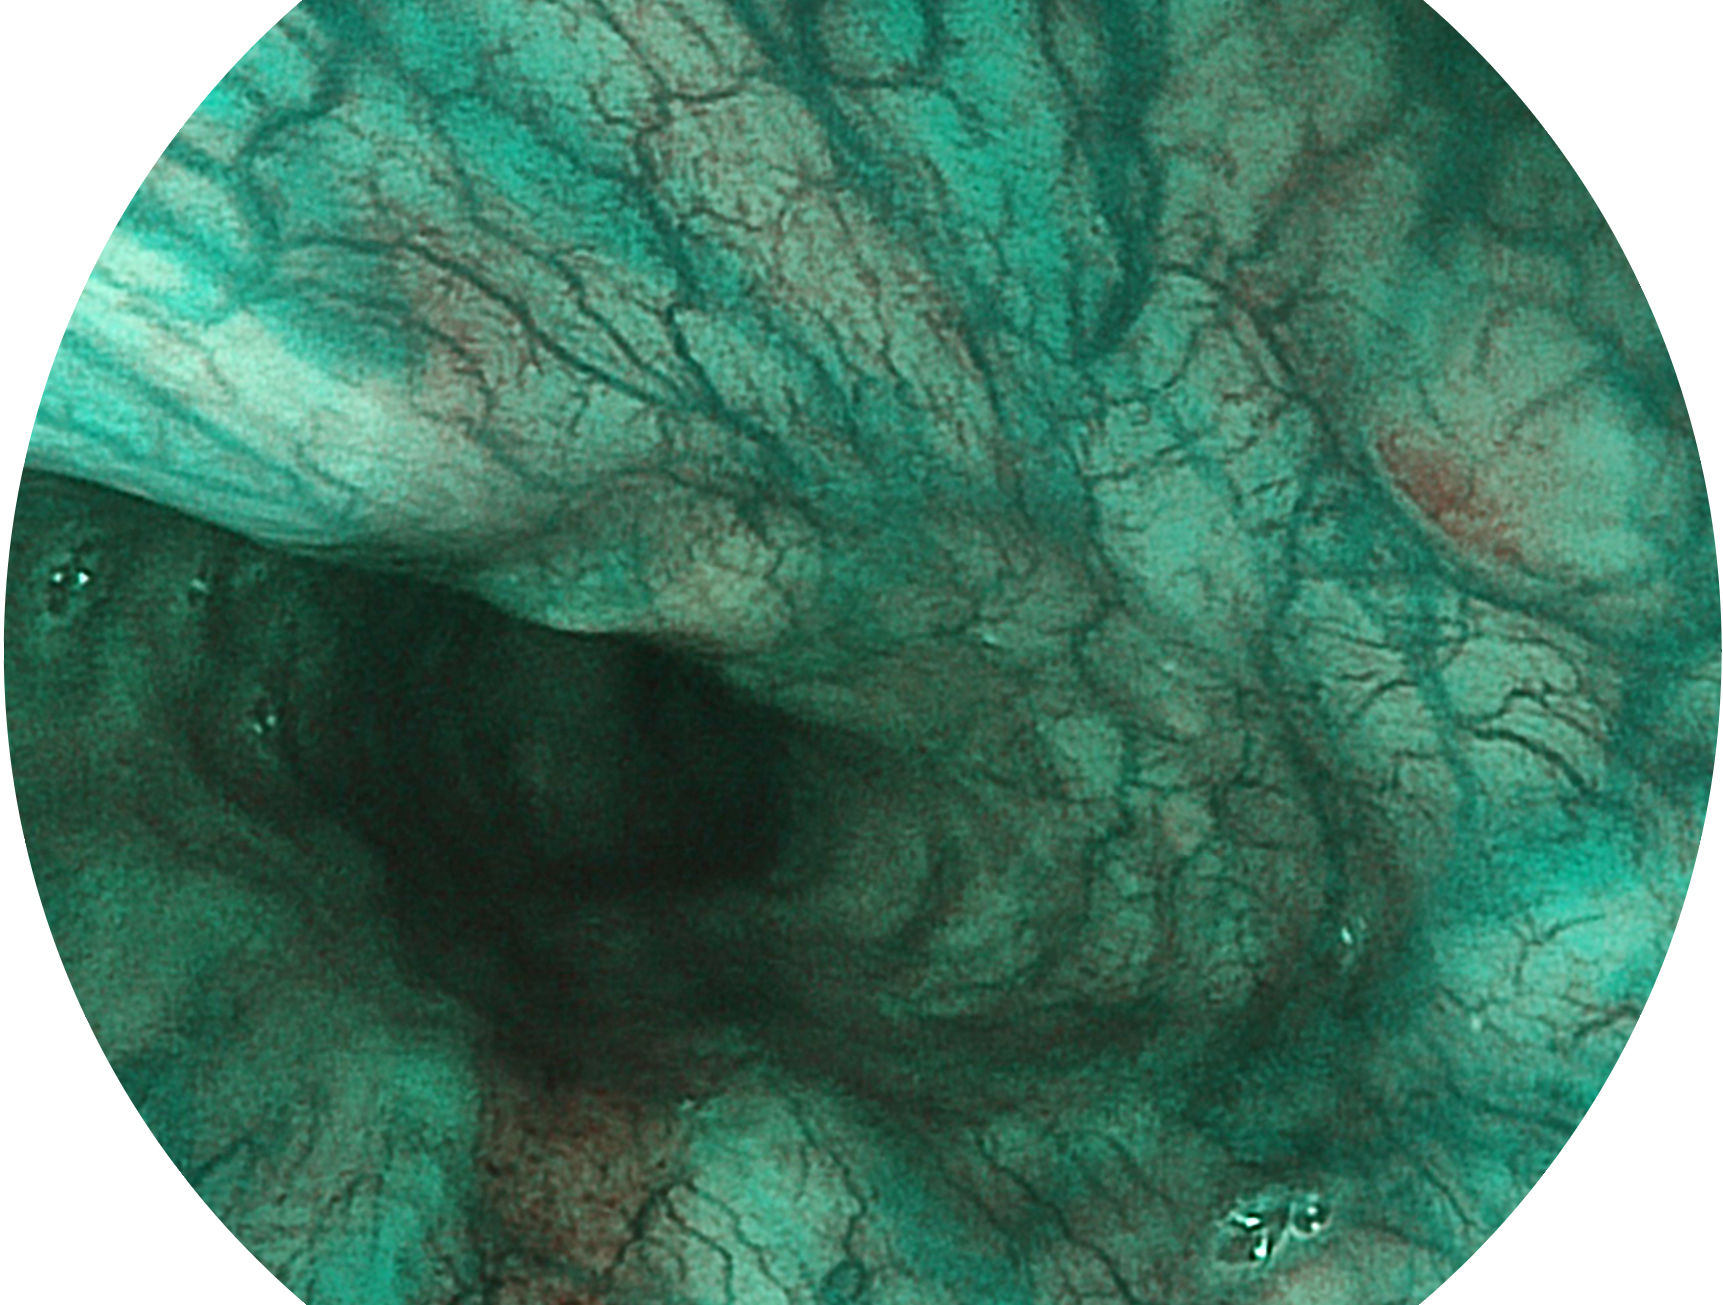

開立新開發(fā)的內(nèi)鏡染色技術(shù),主要是基于多波長LED 光源的開發(fā),VLS-55Q 四波長LED 光源是由四個不同顏色的LED光按照相應(yīng)照明模式所規(guī)定的特定發(fā)光比例進(jìn)行合束后形成,合束后形成的照明光的光譜由紅光、綠光、藍(lán)光及藍(lán)紫光這四個不同的波段范圍構(gòu)成。具有更高光譜自由度,通過光譜比例的控制,實現(xiàn)了聚譜成像技術(shù),英文全稱為“Spectral Focused Imaging, SFI”,縮寫為“SFI”和光電復(fù)合染色成像技術(shù),英文全稱為“Versatile Intelligent Staining Technology, VIST”,縮寫為“VIST”。